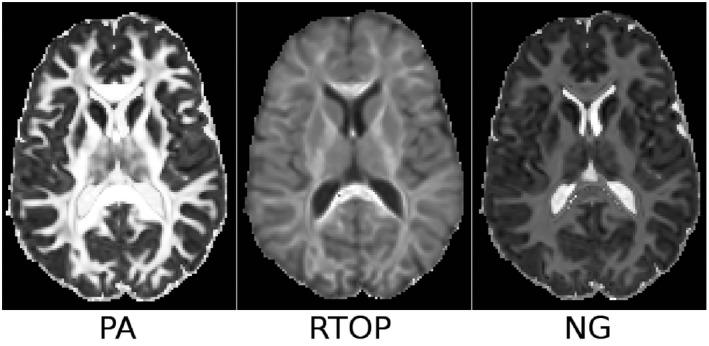

The proposed method evaluates correction performance by measuring variability across datasets of the same object acquired with images having distortions in different directions, thereby overcoming the unavailability of ground-truth, undistorted DWIs. A comprehensive diffusion MRI dataset, collected using a suitable experimental design, is made available to the scientific community, consisting of three DWI shells (Bmax = 5000 s/mm ), 30 gradient directions, a replicate set of antipodal gradient directions, four phase-encoding directions, and three different head orientations. The proposed methodology was tested using the TORTOISE diffusion MRI processing pipeline.

The median variability of the original distorted data was 123% higher for DWIs, 100-168% higher for tensor-derived metrics and 28-111% higher for MAPMRI metrics, than in the corrected versions. EPI distortions induced substantial variability, nearly comparable to the contribution of eddy-current distortions.